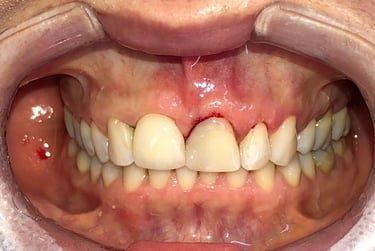

Cirurgia de aumento de coroa clínica antes das coroas

Caso que demonstra a vantagem da integração de diversas áreas da odontologia, unindo cirurgia, periodontia, prótese e estética para alcançar resultados funcionais e harmônicos.

Antes